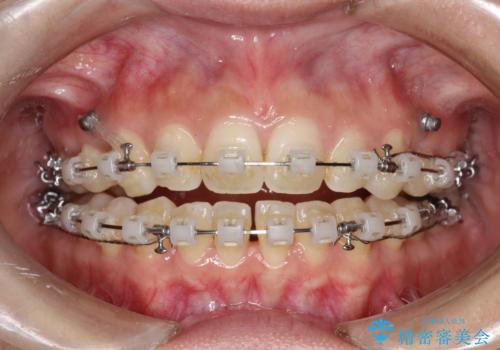

- 矯正装置

- 審美装置

- 出っ歯で口が閉じずらくて、前歯でものかが噛み切れないとのことで来院されました。

上顎の前歯が前方に傾斜して、下顎の前歯と接触していない状態でした。

上顎の前から4番目の歯を両側抜歯して前歯を後方に移動させる計画としました。